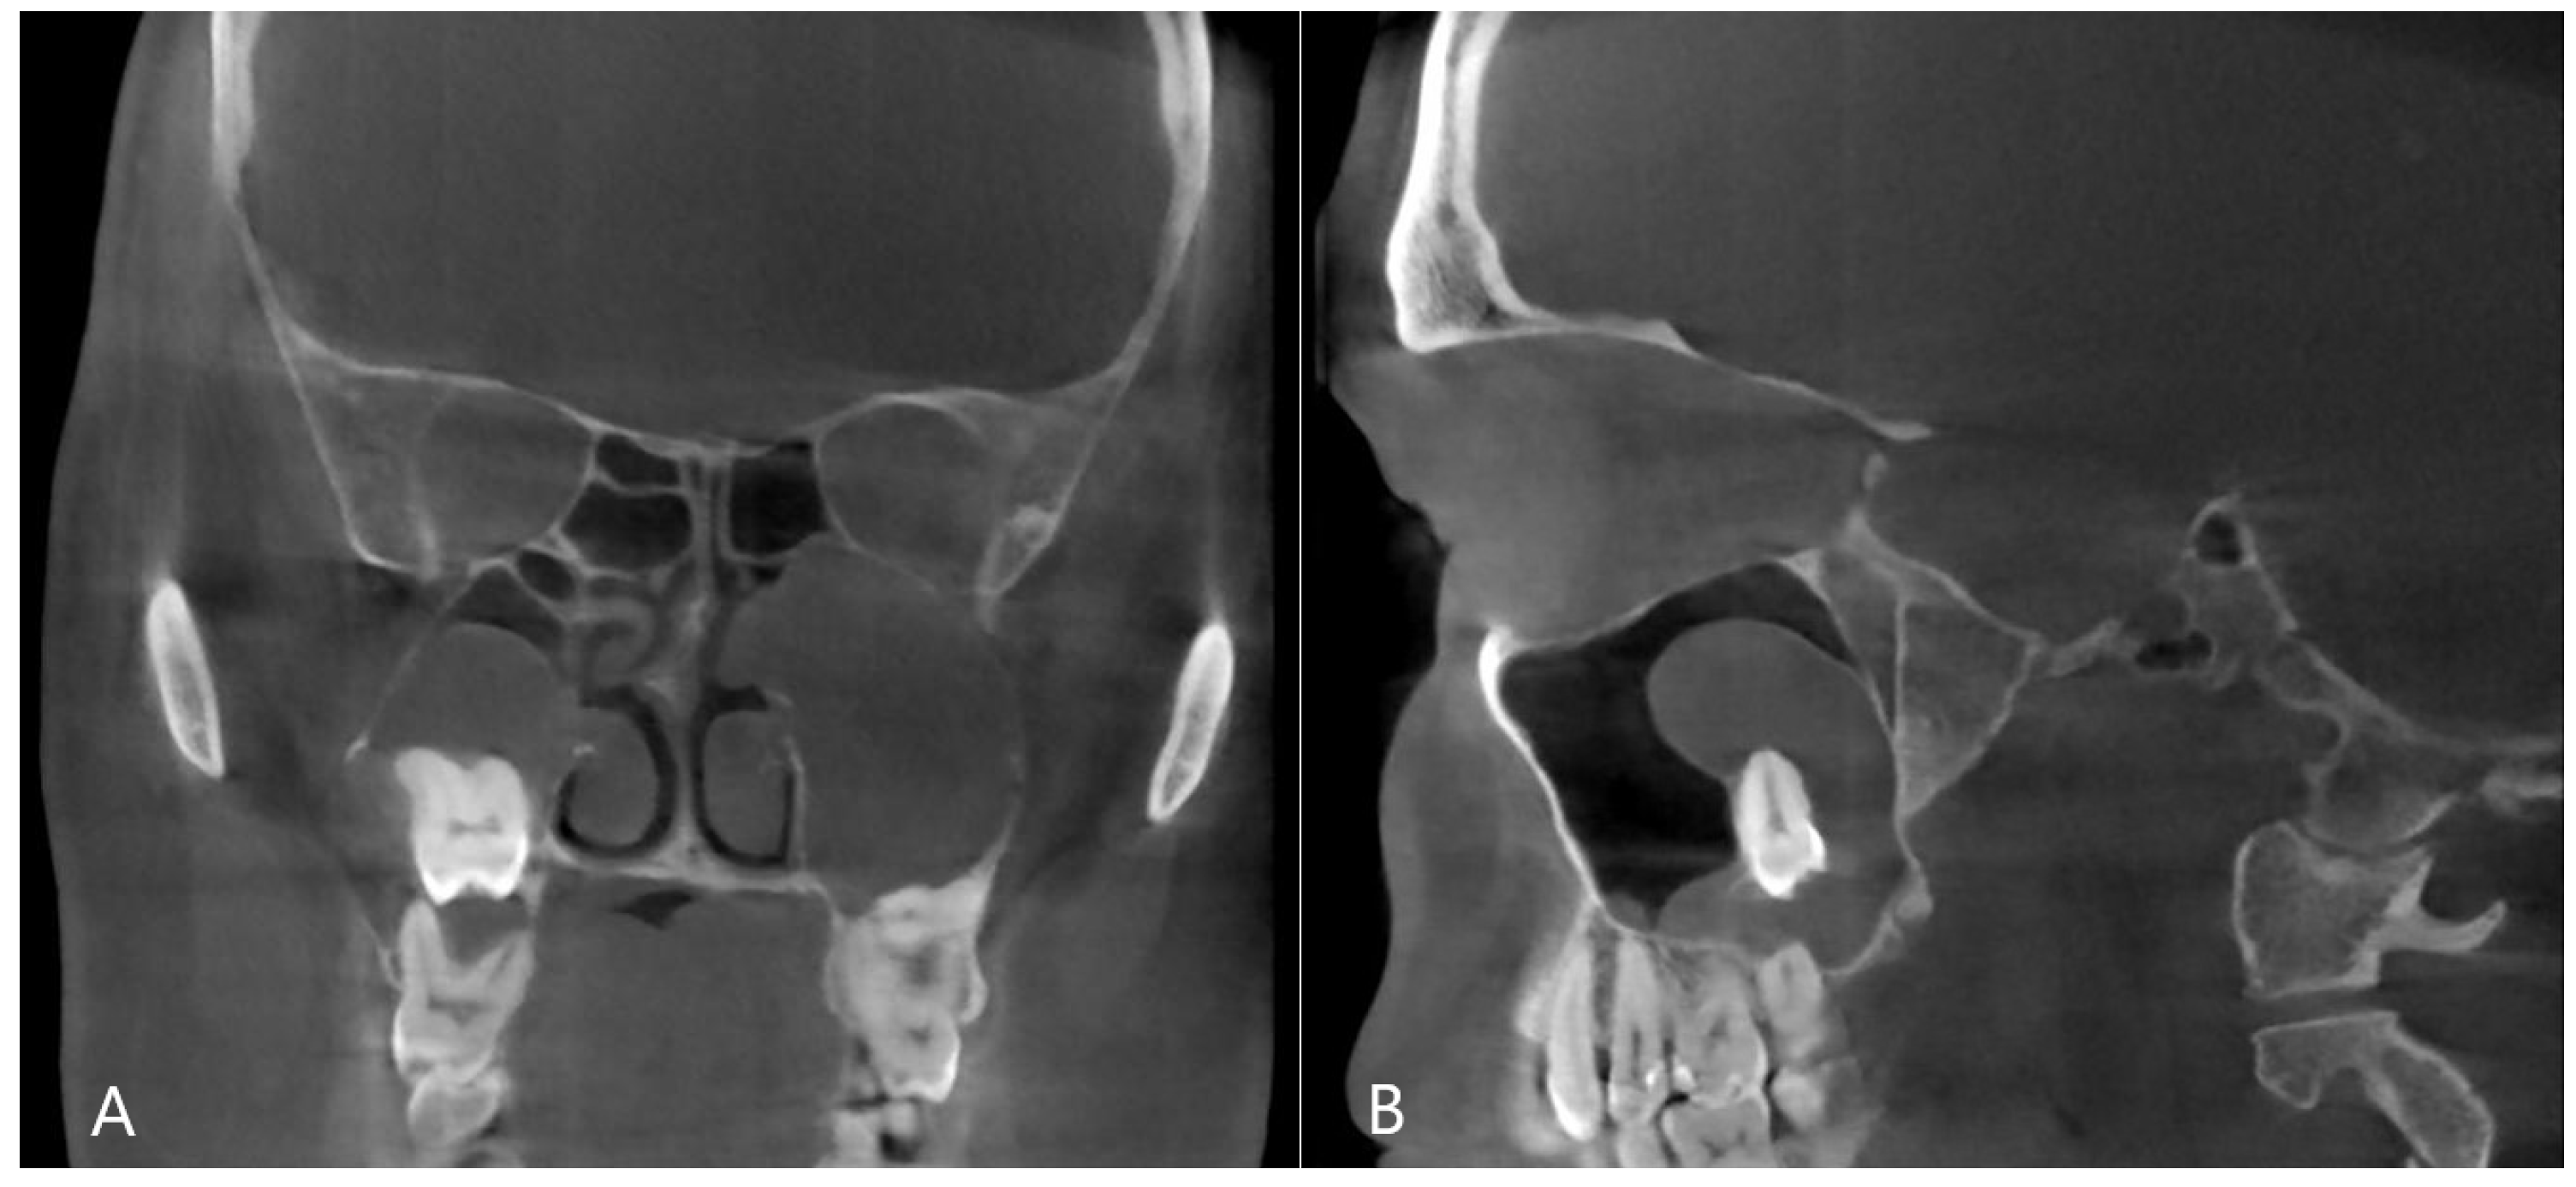

Figure 4. CBCT image of odontogenic cyst with calcified capsule, highly impacted upper wisdom tooth in the right maxillary sinus. Left chronic odontogenic sinusitis caused by impacted left upper wisdom. ((A): coronal, (B): sagittal view).